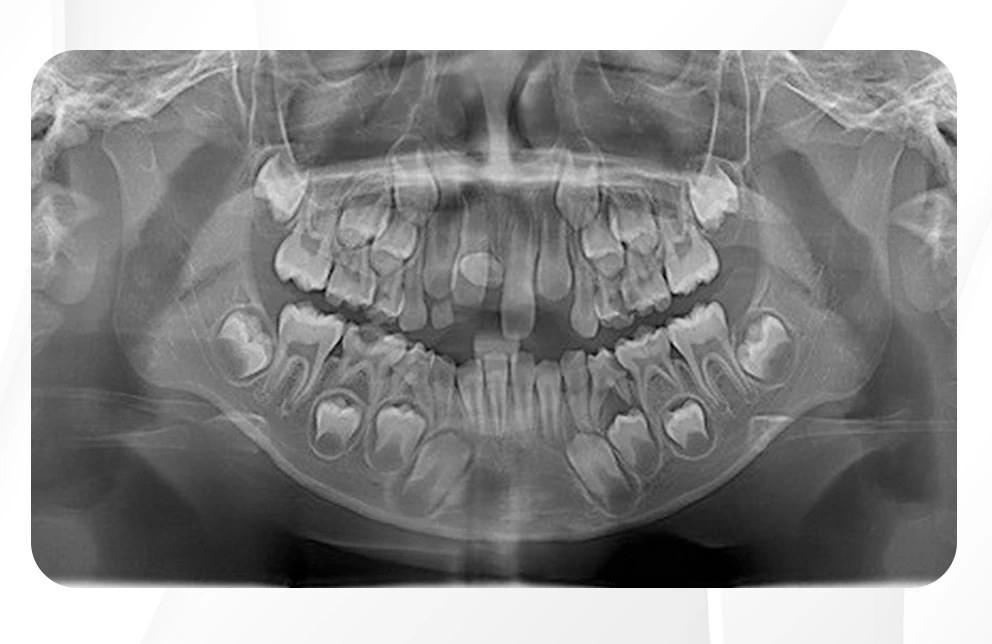

Brezilya'da eşi benzeri görülmemiş bir vaka ile karşılaşıldı. Geçtiğimiz aylarda yapılan bir açıklamaya göre, 11 yaşındaki bir kız çocuğunun ağzında tam 81 diş tespit edildi. Çekilen röntgen filmleri, çocuğun ağzında 18 süt dişi ve 32 kalıcı dişin yanı sıra 31 adet de "süpernümerer" (fazla) diş olduğunu gözler önüne serdi. Yetişkinlerde genel olarak 32 kalıcı diş bulunduğu düşünüldüğünde, otuzdan fazla sayıda süpernümerer dişin bir arada bulunması oldukça nadir bir durum. SADECE BİR TANE DİŞİNİ ÇEKTİRMEK İÇİN HASTANEYE BAŞVURMUŞTU

Başvuruda belirgin bir rahatsızlık belirtisi bulunmadığı ifade edildi. Ancak çekilen röntgen filmleri, çocuğun "çoklu hiperdonti" adı verilen durumu yaşadığını ortaya koydu.

Araştırma ekibi, dişlerin kesin konumunu hassas görüntüleme yöntemleriyle belirledi. Ekip, çoklu hiperdontinin genetik rahatsızlıklarla ilişkili olup olmadığını da titizlikle inceledi.